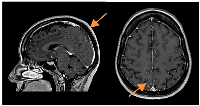

Figure 4

CE and neuraxis MRI response evaluation after 3 cycles of T-DXd.

LMC was noticeably reduced (in extension and intensity).

A slow but steady neurological improvement was achieved, with full autonomy recovery after only three cycles of T-DXd. Response evaluation with CE and neuraxis MRI showed excellent disease response: right parietal lesion was residual and pachymeningeal infiltration was not found; LMC was noticeably reduced (in extension and intensity) (Figures 3 and 4). Toraco-abdominal and pelvic CT (TAP-CT) was systematically negative for new distant secondary disease.